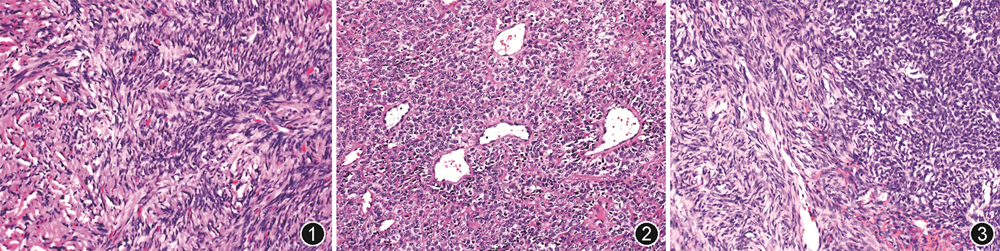

1.病理诊断:中枢神经系统SFT大体上常附着于硬膜上,呈类圆形或卵圆形,界限清楚,切面灰白色、灰褐色,质韧或质软,有时可伴有黏液变,恶性病例则常见出血、坏死和囊性变等。中枢神经系统SFT组织学形态与软组织SFT一样,低倍镜下,肿瘤可呈经典SFT形态(图1)、HPC形态(图2)或二者混合存在(图3)。经典SFT形态镜下表现常为疏密交替,呈“无结构”生长模式,肿瘤细胞梭形,形态温和,间质可见粗细不等的胶原纤维束及薄壁血管;经典HPC形态表现为细胞丰富、致密,大小相对一致,胞质少,核圆形、卵圆形,染色质细腻,间质富于鹿角状分支血管。除了典型的SFT或HPC组织学表现,个别病例可呈现罕见组织学形态,如乳头样、伴黑色素细胞分化[21]和脂肪化生等,少见情况间质可出现不同程度的黏液变、出血和囊性变。恶性病例常出现不典型表现,表现为细胞密度增加、异型性明显、核分裂象增多或坏死等。